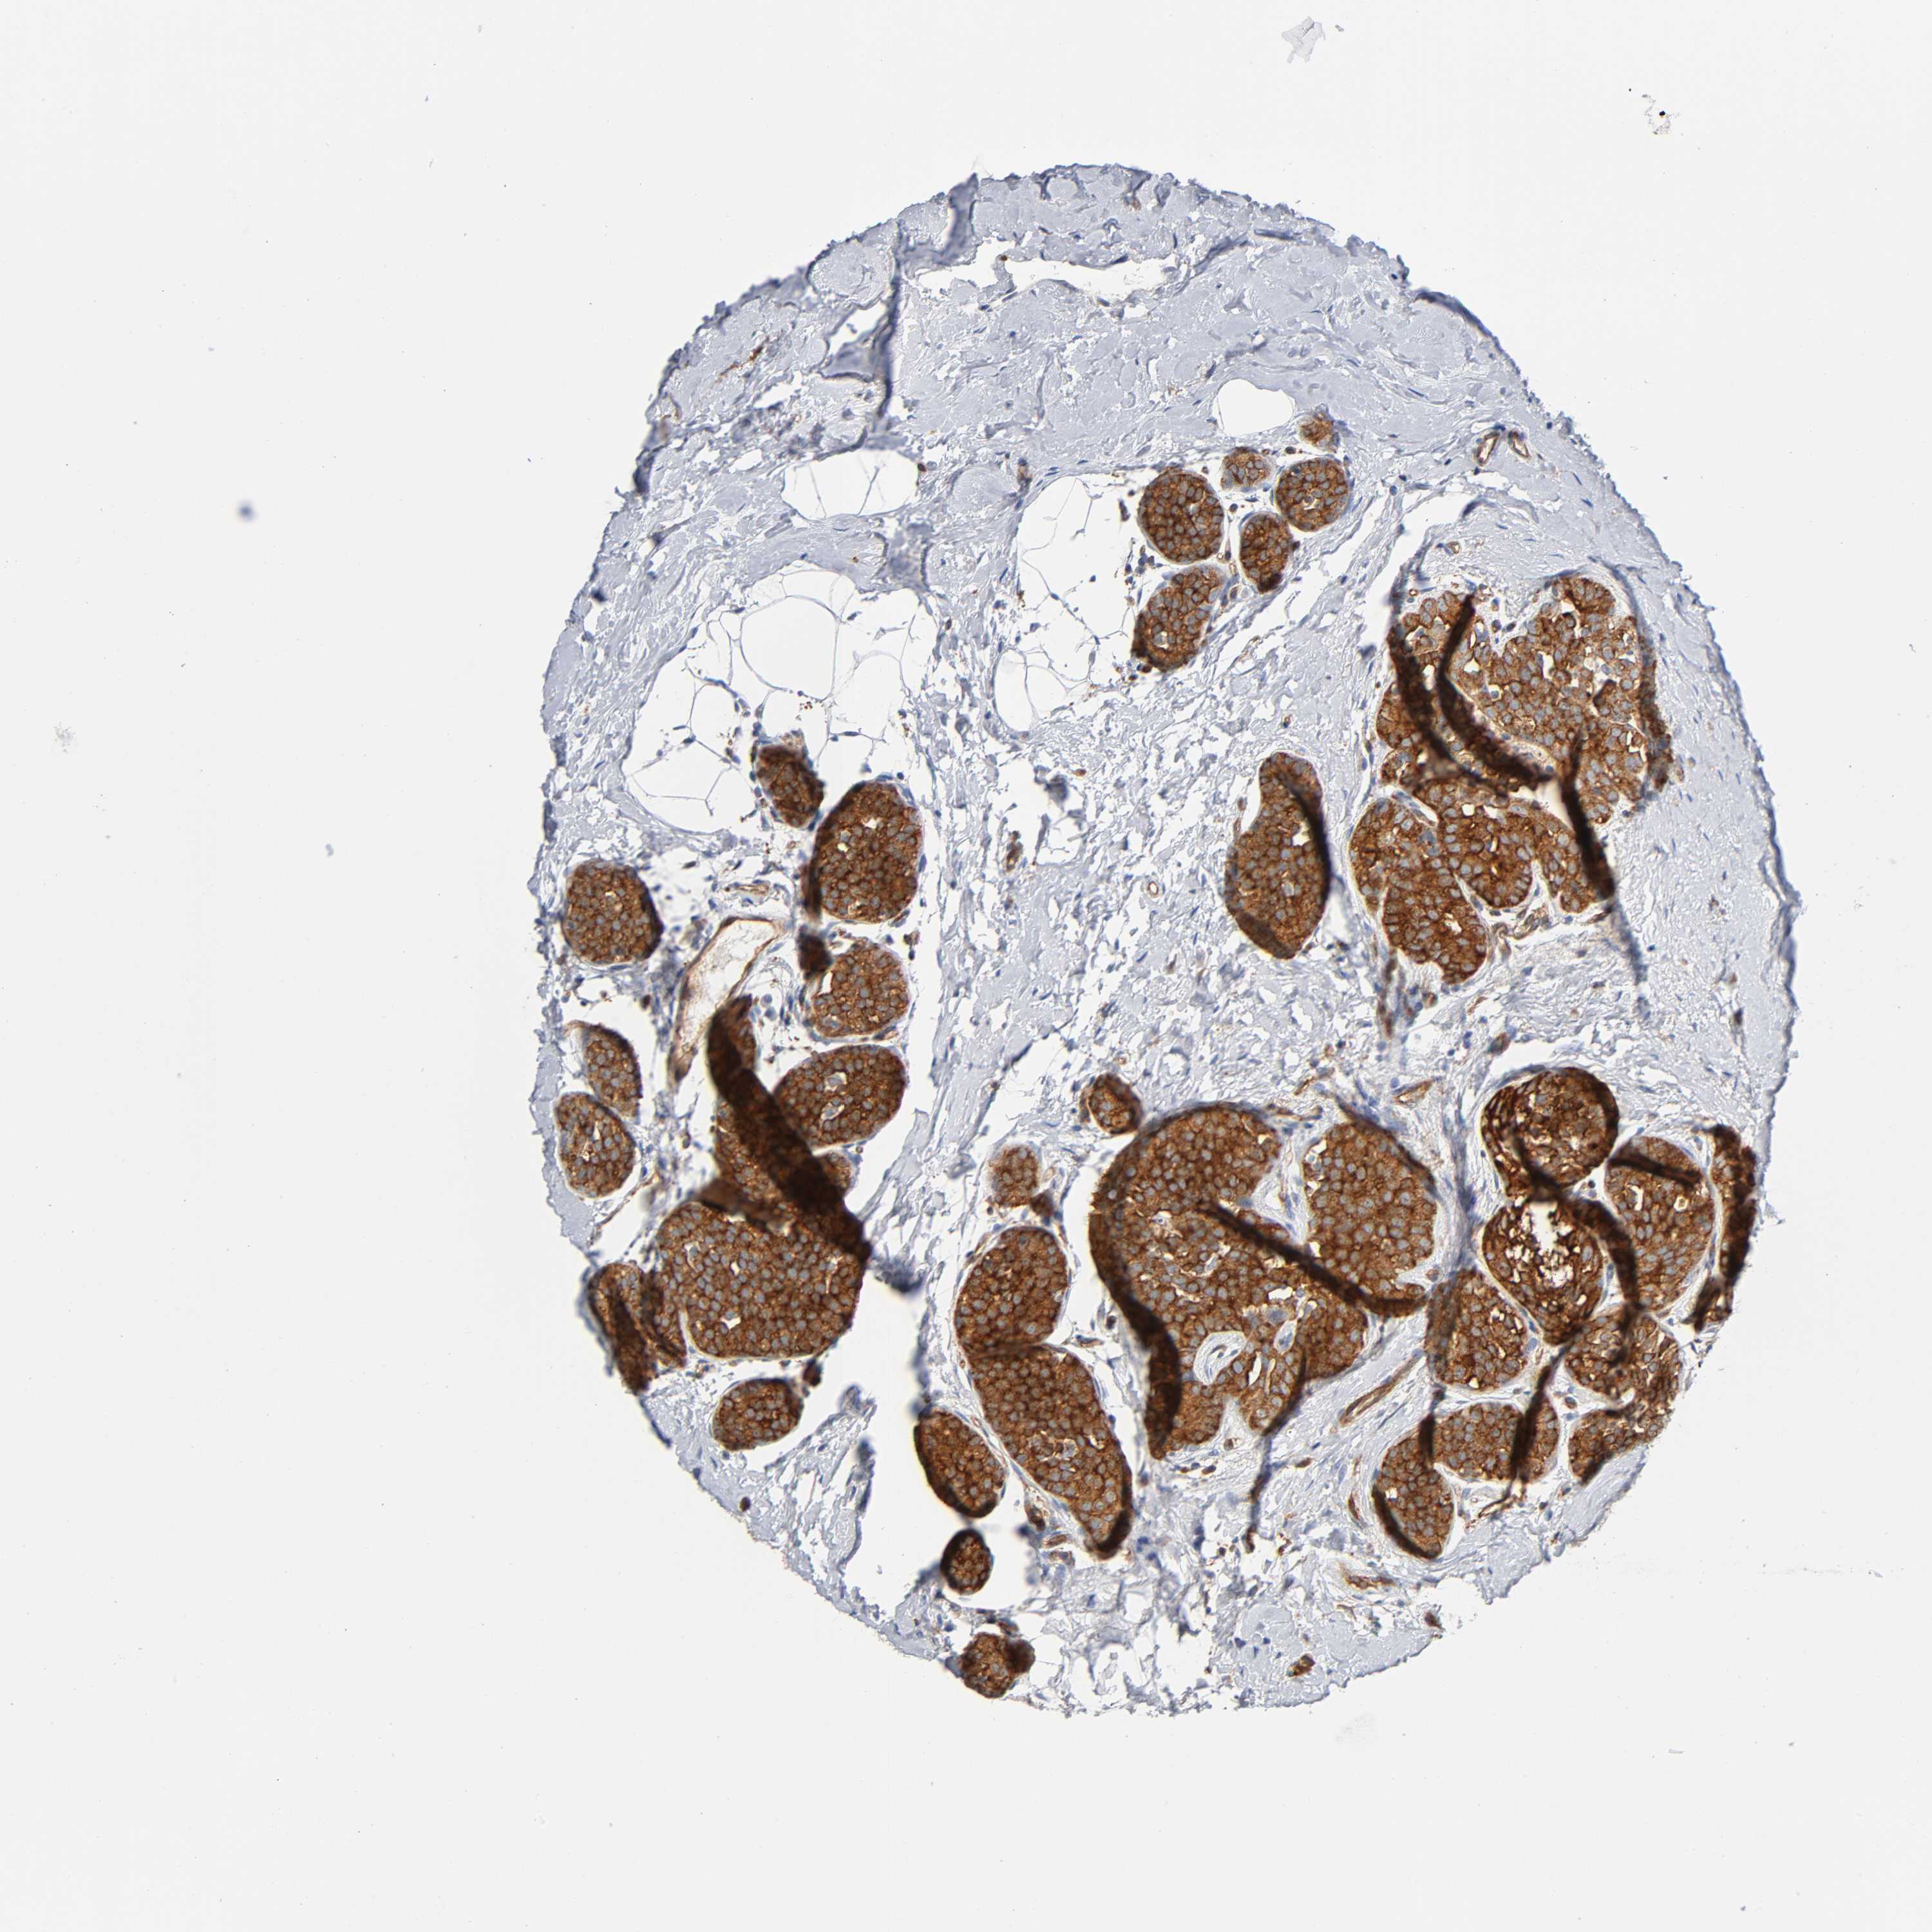

BRCA TCGA BRCA VALIDATION PROTEIN EXPRESSION

ANTIBODIES

AND

VALIDATION